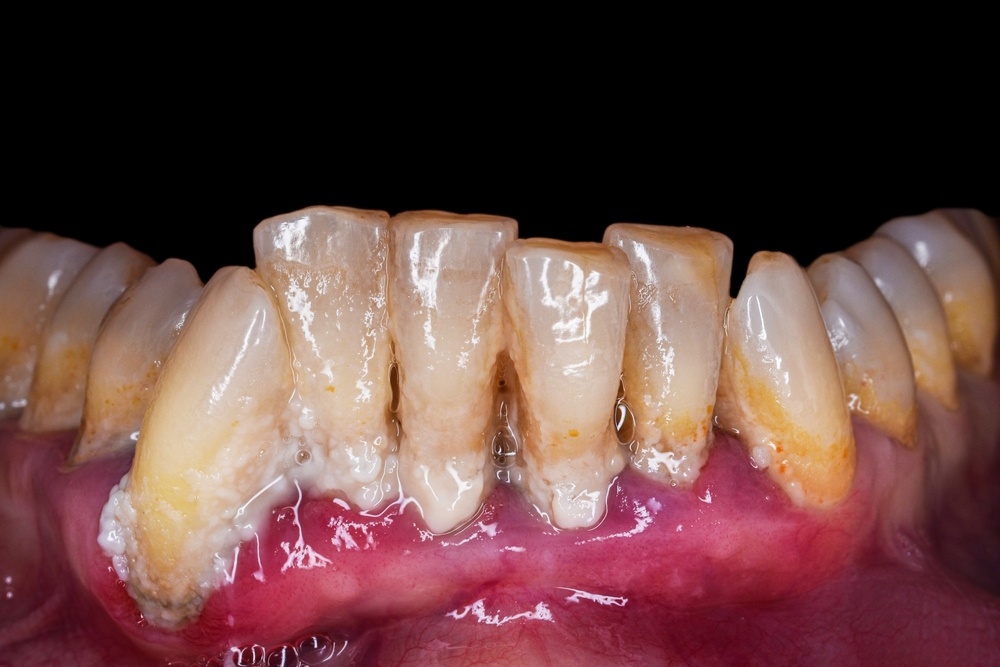

Зубной камень — твердый налет, который образуется на поверхности зубов. Он формируется из налета — мягкого биопленочного образования, состоящего из бактерий, остатков пищи и слюны. Этот процесс начинается с момента, когда налет не удаляется с поверхности зубов.

Зубной камень классифицируется по месту локализации:

• Наддесневой. Образуется выше уровня десны и заметен сразу, даже при обычном осмотре зубов. Цвет налета: темный или с желтым оттенком.

• Поддесневой. Не виден при осмотре и локализуется ниже уровня десны. Среди основных симптомов — синюшный цвет, отечность и кровоточивость десны.

Если камень находится под десной, то патология является признаком развития пародонтита и может быть связана с разрушением костной ткани зуба. Часто его диагностируют при проведении пародонтологических операций или при зондировании пародонтальных карманов.